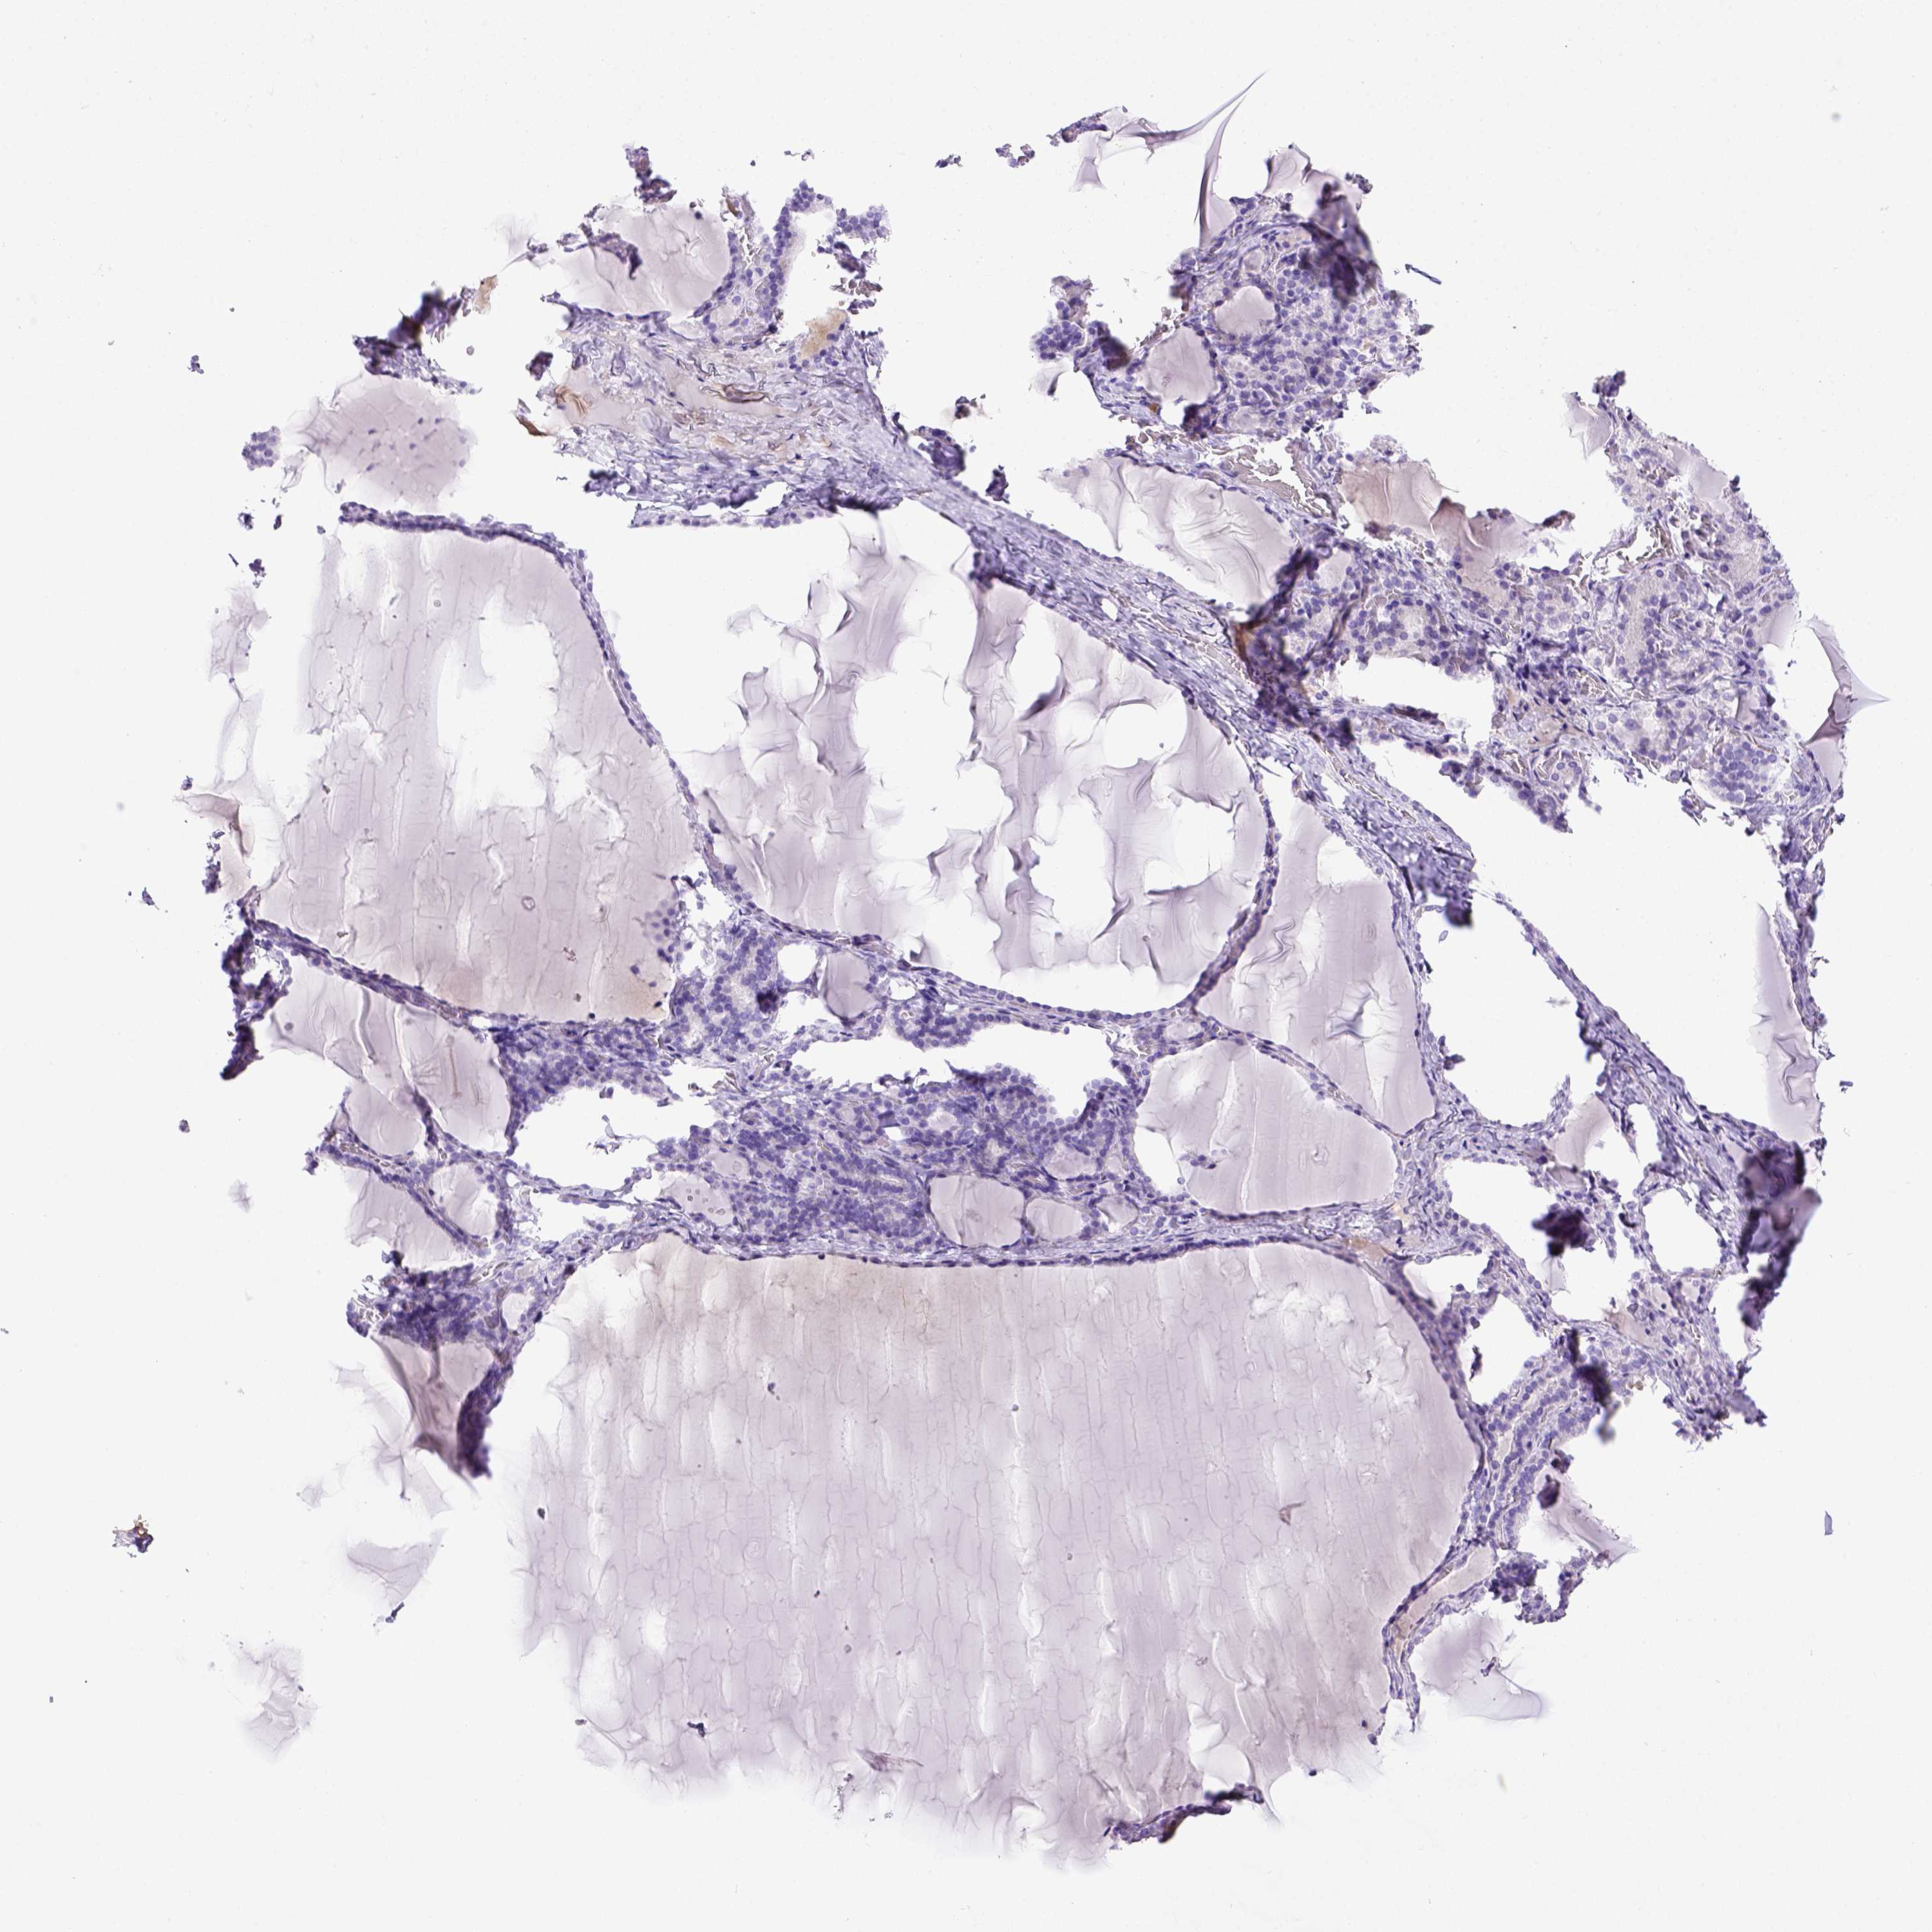

THYROID GLAND - Antibody stainingi

Antibody staining in the annotated cell types in the current human tissue is reported as not detected, low, medium, or high, based on conventional immunohistochemistry profiling in selected tissues. This score is based on the combination of the staining intensity and fraction of stained cells.

Each image is clickable and will lead to virtual microscopy that enables deeper exploration of all samples and also displays staining intensity scores, fraction scores and subcellular localization as well as patient and tissue information for each sample.

Antibody HPA001835Antibody HPA003948Antibody CAB072872

Glandular cells Not detectedNot detectedNot detected